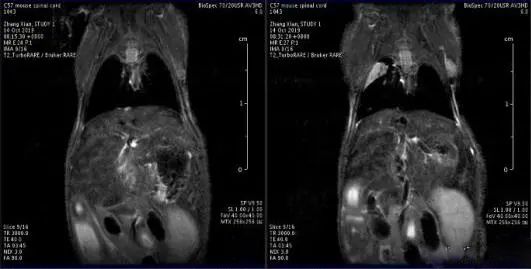

第三:小動物核磁。小動物核磁技術(shù)可以更明細那地觀察到腫瘤細胞在肝臟,肺臟或者其他器官的轉(zhuǎn)移情況

7dd98d1001e93901d3d5386ebe8d11ef37d19671.webp

核磁檢測